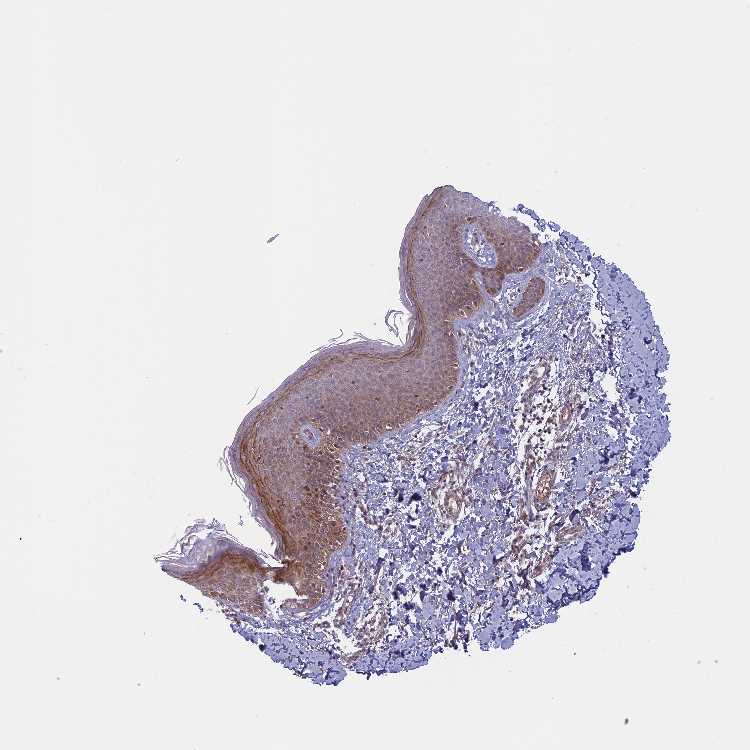

SKIN 1 - Antibody stainingi

Antibody staining in the annotated cell types in the current human tissue is reported as not detected, low, medium, or high, based on conventional immunohistochemistry profiling in selected tissues. This score is based on the combination of the staining intensity and fraction of stained cells.

Each image is clickable and will lead to virtual microscopy that enables deeper exploration of all samples and also displays staining intensity scores, fraction scores and subcellular localization as well as patient and tissue information for each sample.

Antibody HPA042705

Langerhans Medium

Fibroblasts Low

Keratinocytes Medium

Melanocytes Medium